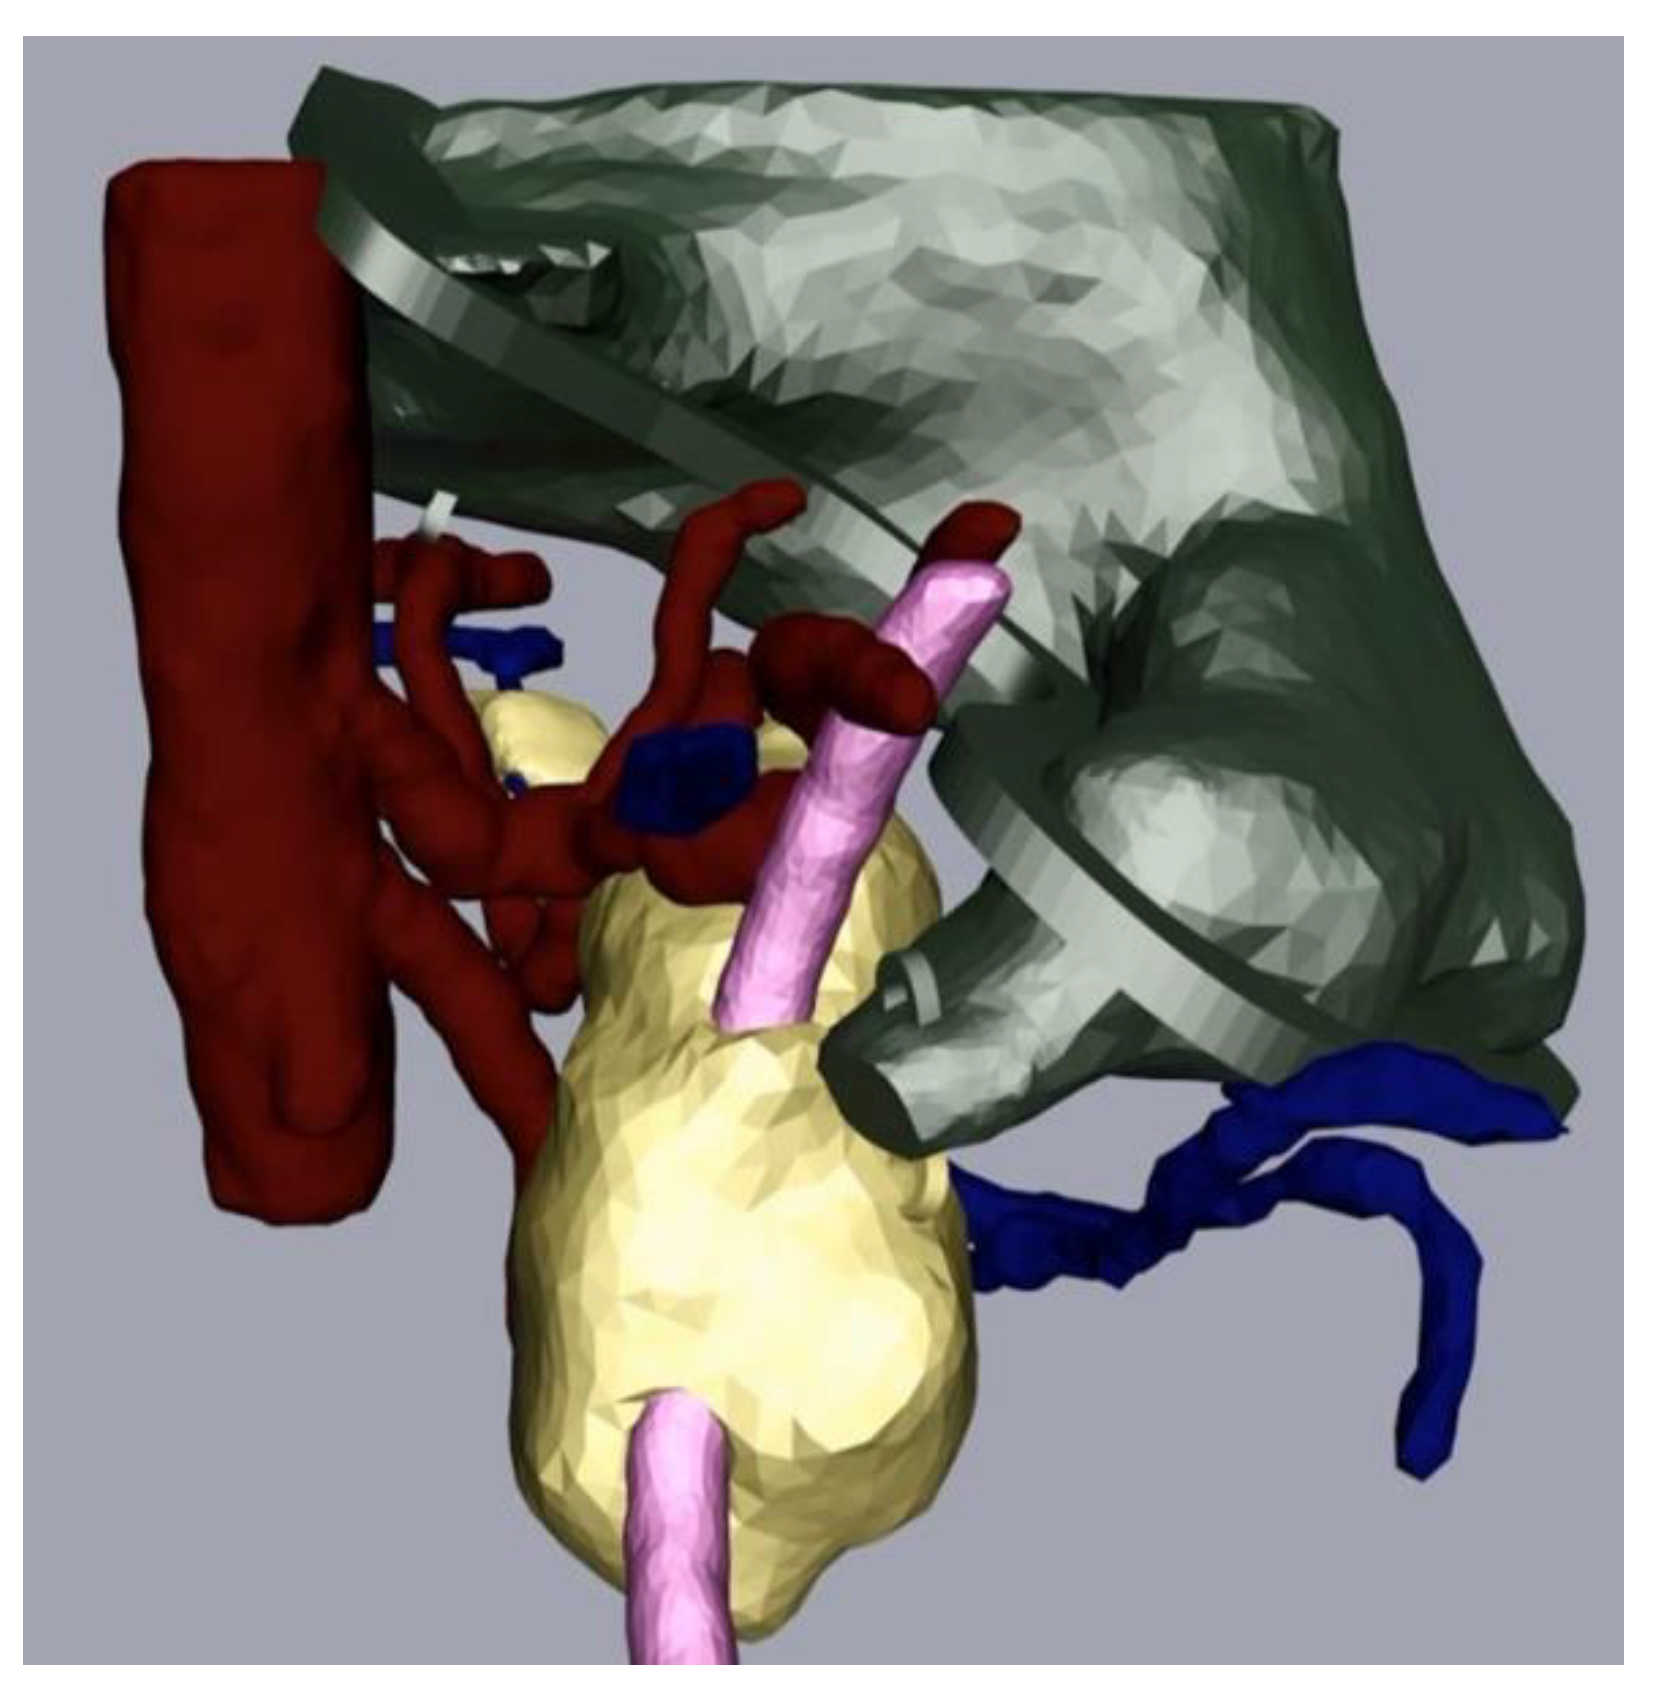

Figure 3.

After completion of the final mesh, the pancreas and its surroundings can be viewed from different angles. Note the rather rough surface as the CT scans had a slice thickness of 1 mm. (The pancreas in yellow, the arteries in light blue, the veins in dark blue, and the splint in pink.)